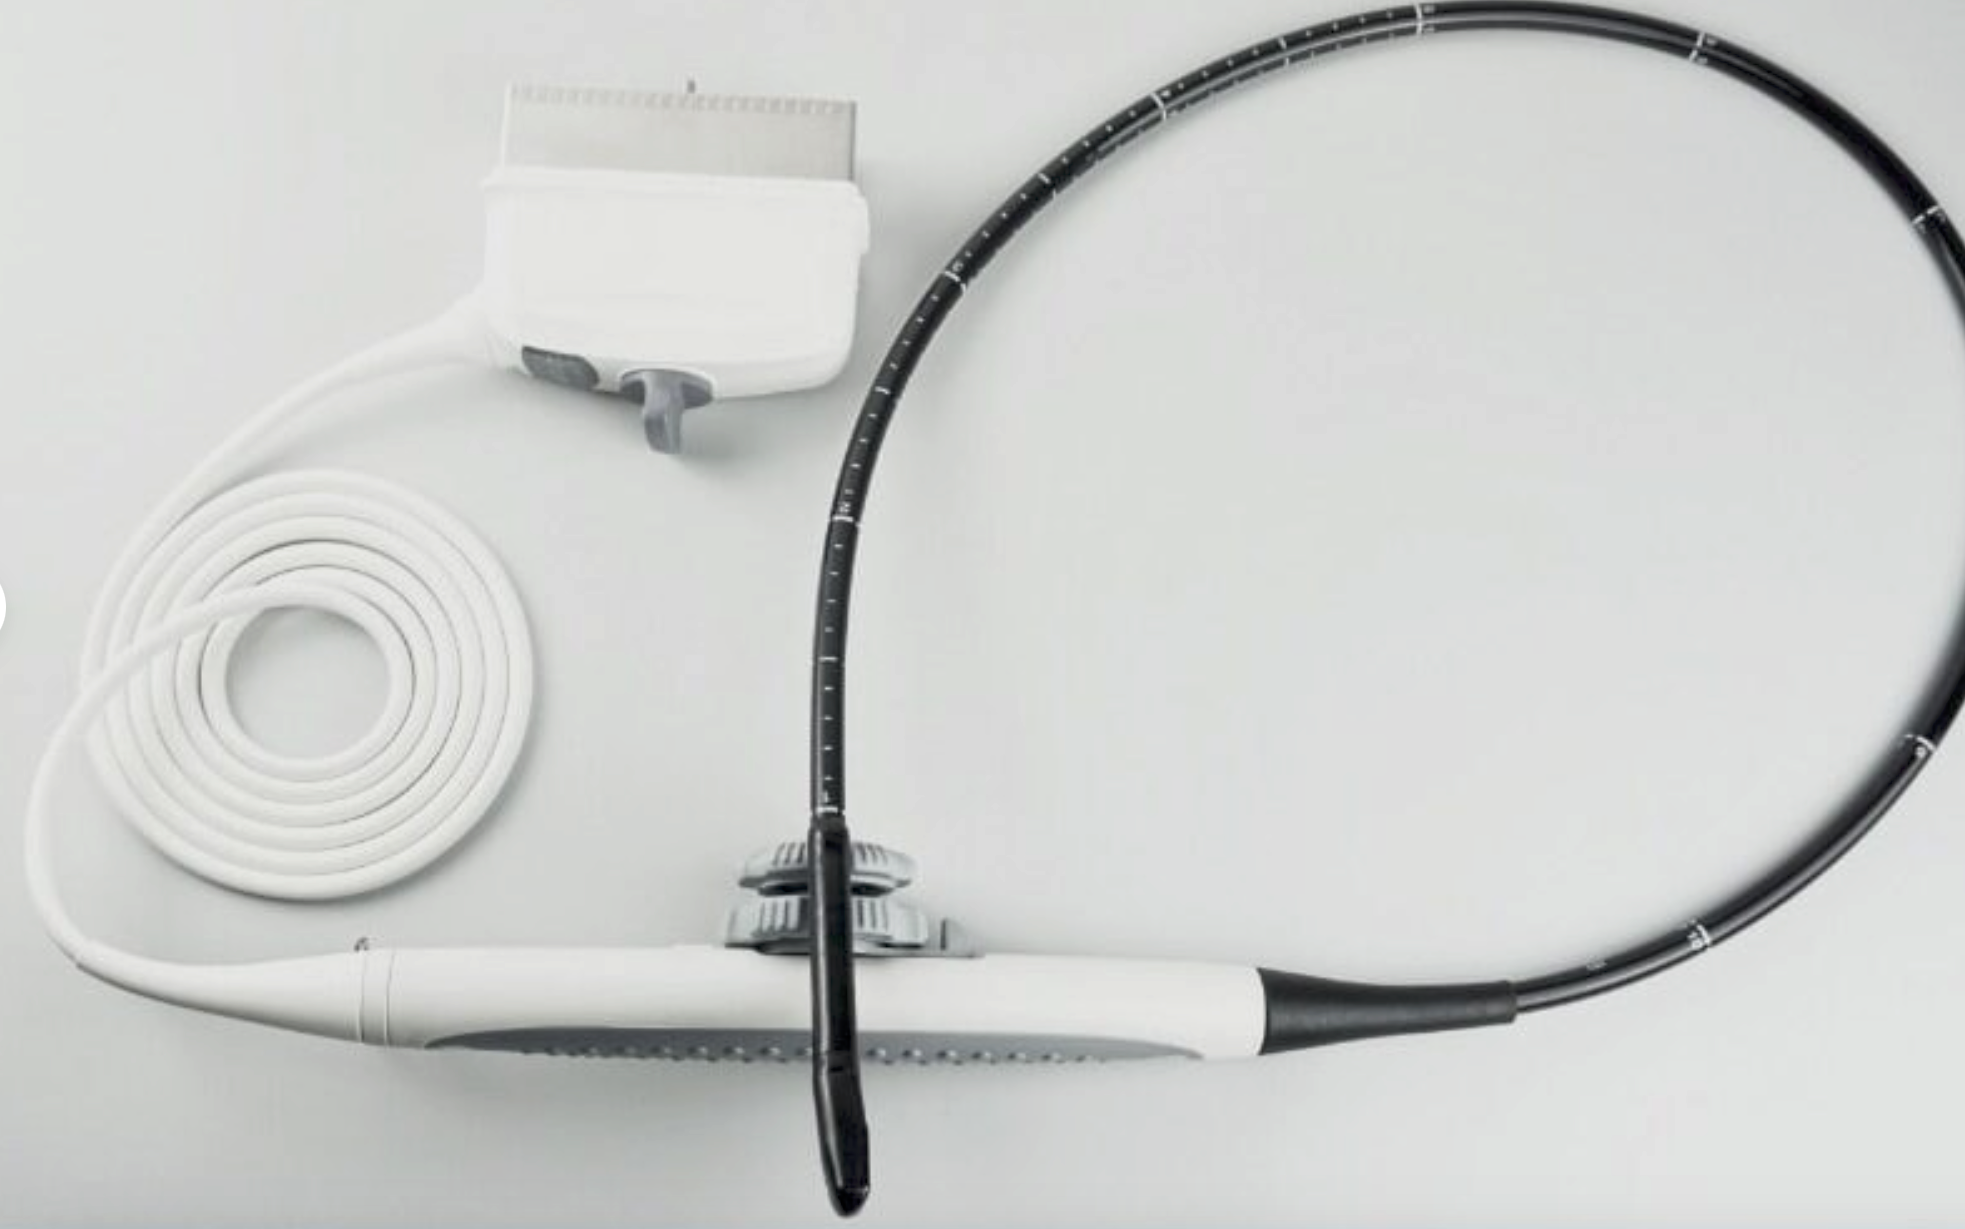

Designed with portability and functionality in mind, the New Portable Notebook Digital Laptop Machine offers superior performance without compromising on ease of use. Its compact size allows for easy transport and setup, while the digital laptop interface ensures that users can quickly access and utilize the scanner's capabilities. The inclusion of a convex probe and 3D imaging further enhances the diagnostic accuracy, providing clearer and more detailed images than ever before.

In addition to its user-friendly design, the New Portable Notebook Digital Laptop Machine provides high-resolution imaging that is crucial for accurate diagnostics. The 3D imaging capability allows for more comprehensive assessments of anatomical structures, leading to better treatment planning and patient management. Whether used for routine check-ups or complex medical evaluations, this ultrasound scanner delivers reliable and precise results.